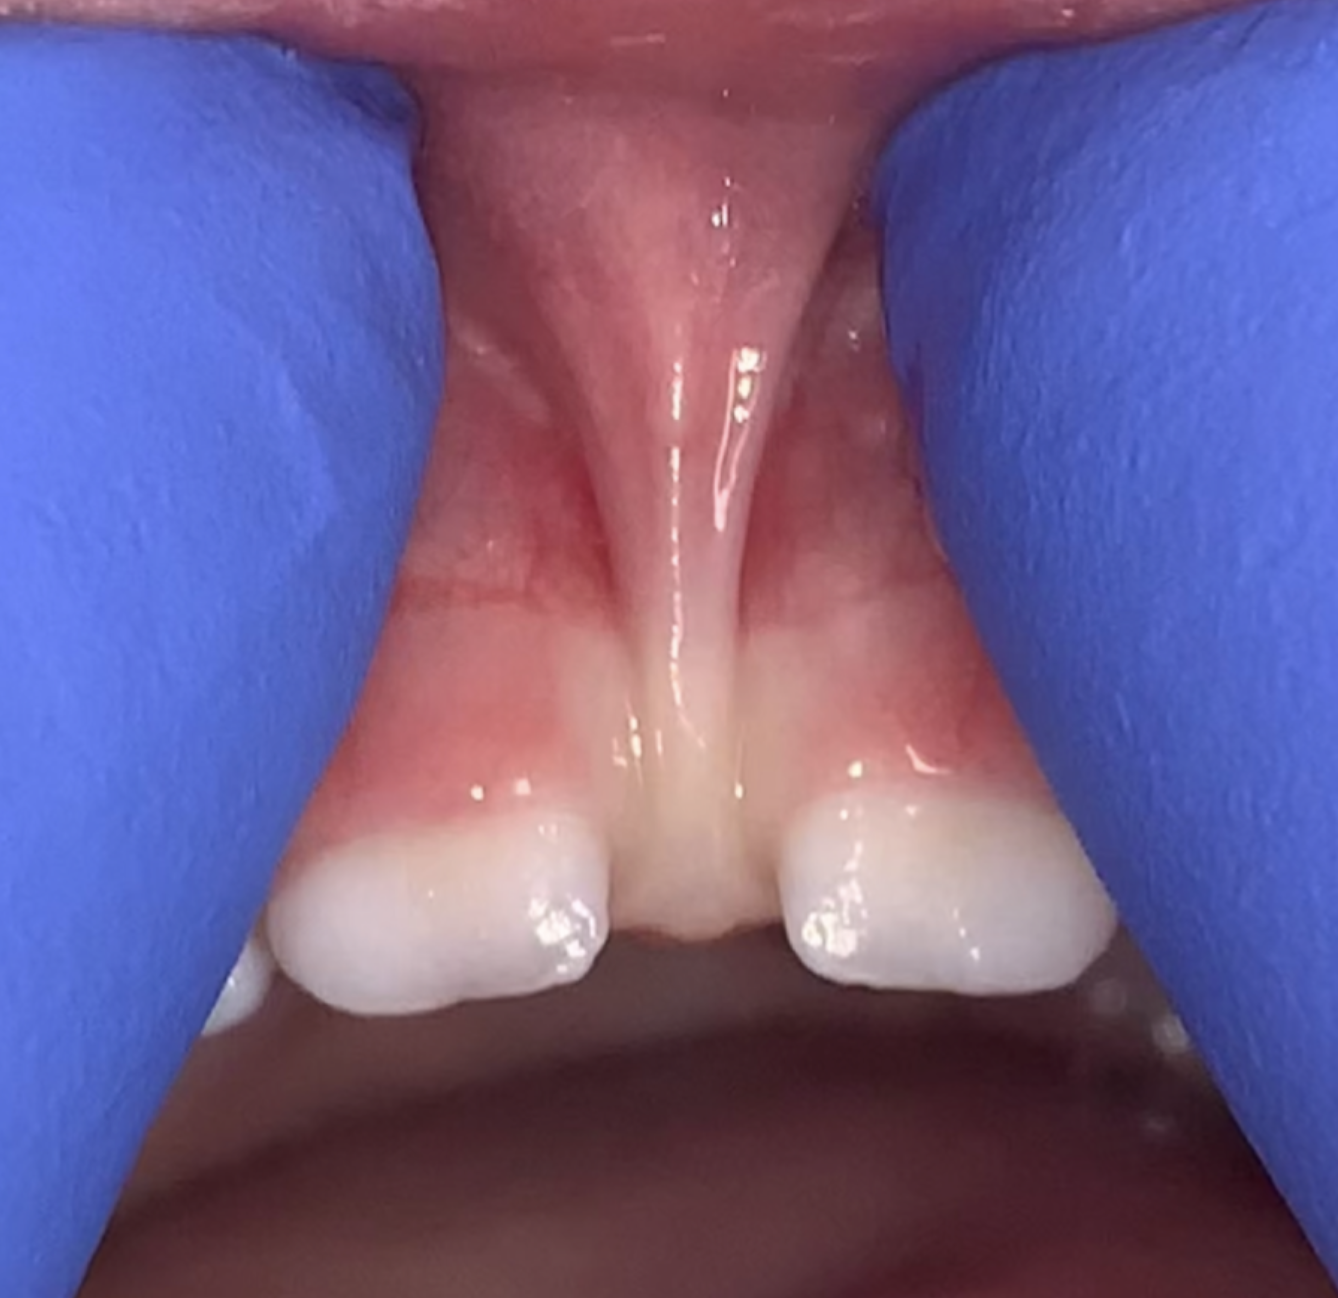

In your mouth, you should see a band of tissue that connects the lips to the gums or the tongue to the floor of the mouth. This band is called a frenulum or frenum and is a mucosal attachment containing muscle and connective tissue fibers. At times when the frenum restricts normal movement, your baby or child may need special care for mobility and comfort.

Lip Ties

A lip tie is a labial frenulum that is abnormally tight or thick. It can cause difficulty lifting the lip as required for nursing, feeding, speech, or for cleaning the teeth.